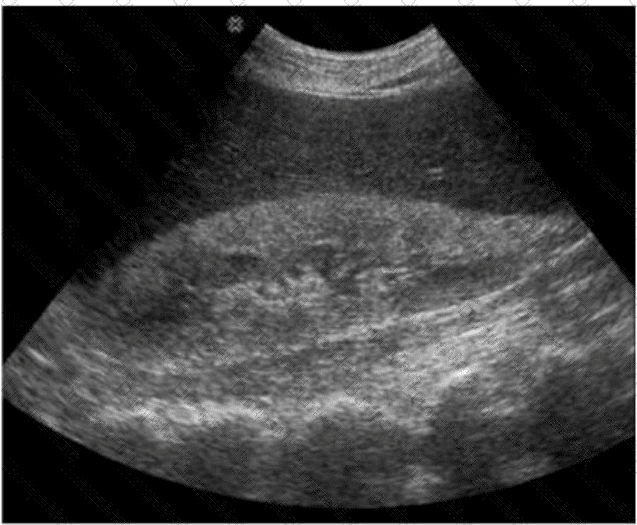

Questions 33

Which diagnosis is most consistent with this image from a patient with acute scrotal pain?

AB-Abdomen Question 33

Options:

A.

Scrotal abscess

B.

Testicular rupture

C.

Testicular torsion

D.

Epididymitis